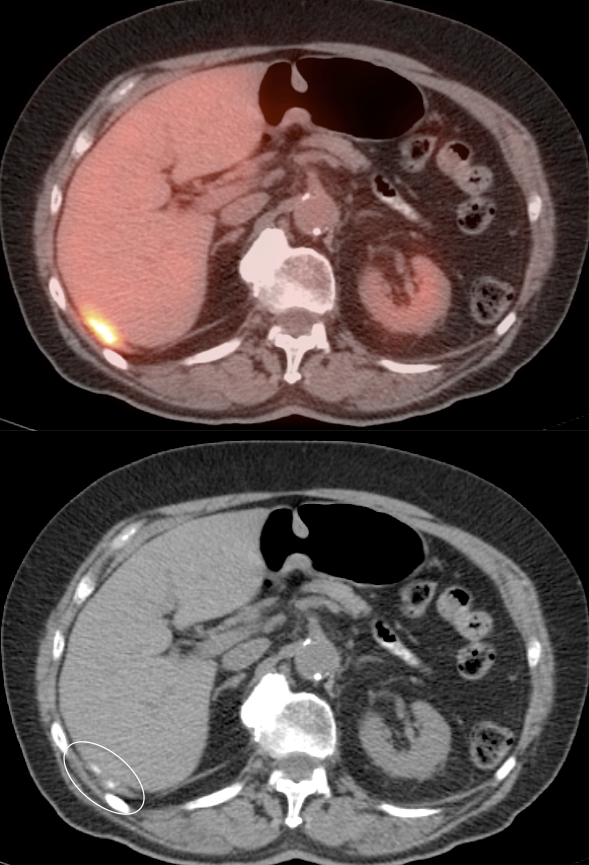

- Distant Disease: Most commonly to the bones, lymph nodes, lung, liver and brain.

PET/CT imaging has traditionally been considered less sensitive than a conventional bone scan for blastic metastases (e.g. prostate & breast cancers).

Recent literature, however, suggests that while a bone scan may be more sensitive than a PET scan alone for blastic lesions, it may be actually less sensitive when compared to a PET scan plus a CT scan (e.g. a PET/CT scan).